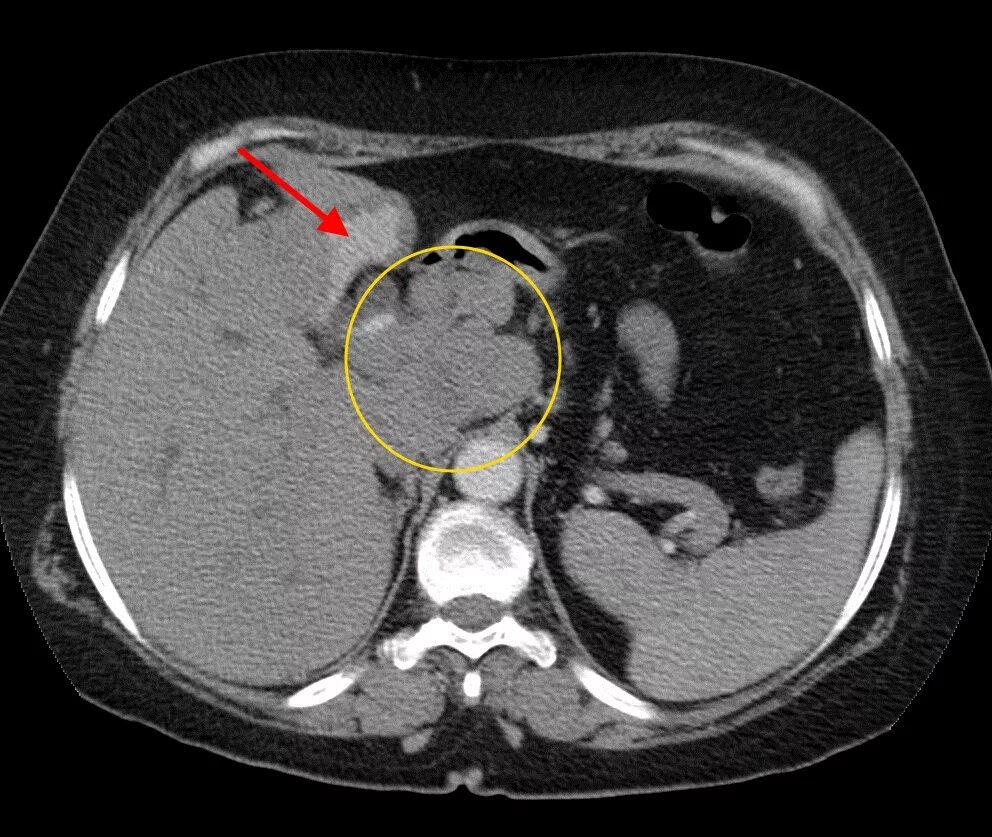

Мрт кисты поджелудочной